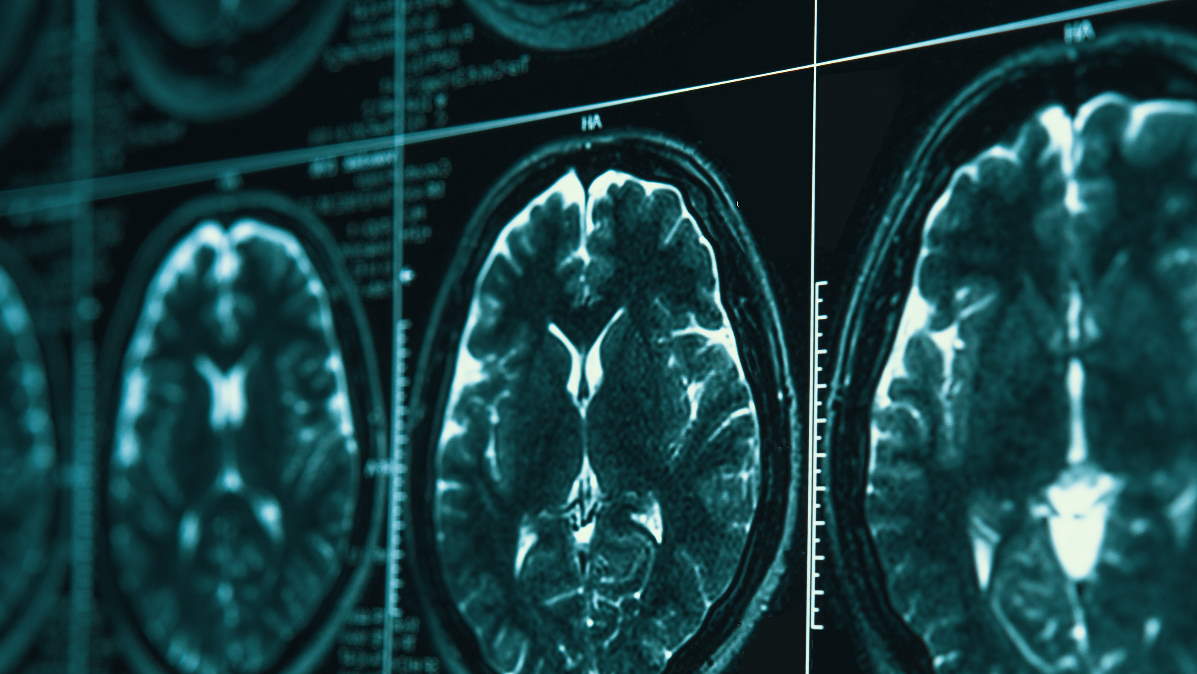

Το υπερηχογράφημα και το τρίπλεξ είναι μία μόνο από τις πολλές απεικονιστικές μεθόδους που υπάρχουν στην ιατρική φαρέτρα για την απεικόνιση του σώματος και την ανάδειξη της όποιας παθολογίας. Η απλή ακτινογραφία, αξονική τομογραφία (CT) και η μαγνητική τομογραφία (MRI) είναι από τις πιο ευρέως διαδεδομένες μεθόδους απεικόνισης στην ιατρική πράξη.